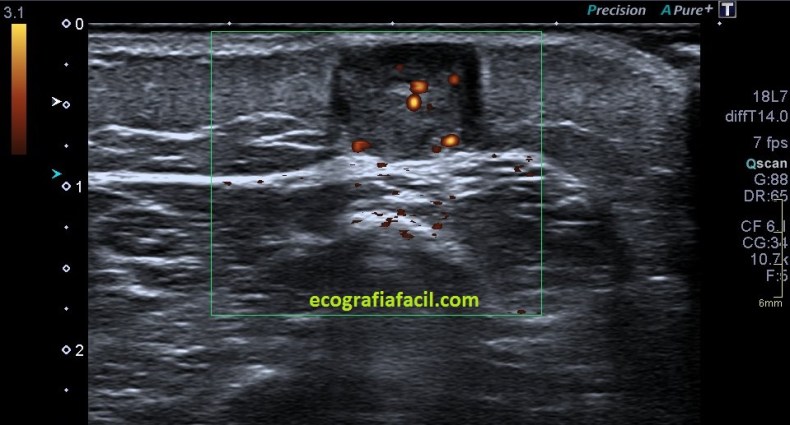

La ecoestructura tumoral era hiperecogénica, ovalada, heterogénea, con ligera presencia de líquido alrededor del tumor, tumor que no infiltraba anatomía colindante y  cuya que además poseía muy poca vascularización…

Cortes en eje corto y eje largo para poder hacer medidas, imágenes 5 y 6 y luego, el doppler, 7 y 8 donde se demostró mínima vascularización interna y dos «grandes» vasos laterales, arteriales.